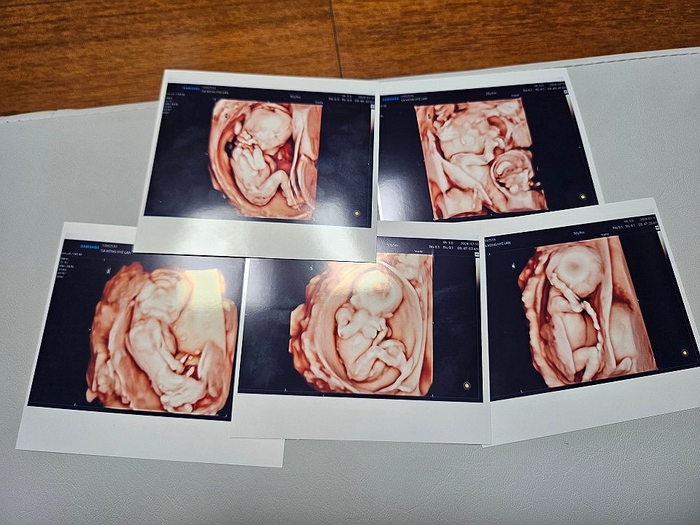

Siêu âm 5 con của vợ chồng Kim và Sagong. Ảnh: Yonhap